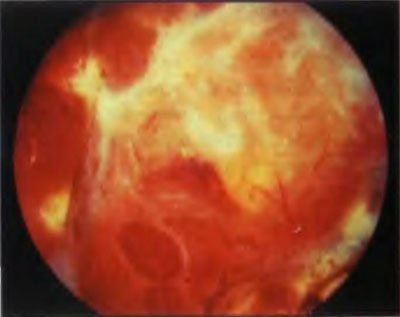

When retinal detachment the vitreous body never remains indifferent. In the initial period, only small violations of its structure are observed, manifested in the form of various inclusions floating in the field of view. With a long-existing detachment in the framework of the vitreous body, strands develop, which, like ropes, attach to the retinal surface and, slowly contracting, retract the retina to the center of the eyeball. This process is called vitreoretinal proliferation, which ultimately leads to the formation of the so-called «funnel» retinal detachment. In such a situation, reconstructive surgery is required, in terms of the quality of a much higher level. Close this gap seals is almost impossible, and not enough. The main task is to clean the surface of the retina from the strands of the vitreous body, straightening it.

当视网膜脱离时,玻璃体永远保持冷漠。 在最初阶段,仅观察到其结构的一些小违规,表现为视野中漂浮的各种夹杂物。 随着玻璃体框架内长期存在的脱离,会形成股线,就像绳索一样,股线会附着在视网膜表面,然后缓慢收缩,使视网膜缩回眼球中心。 该过程称为玻璃体视网膜增生,其最终导致形成所谓的“漏斗”视网膜脱离。 在这种情况下,就更高水平的质量而言,需要进行重建手术。 封闭这种间隙密封几乎是不可能的,而且还远远不够。 主要任务是清洁玻璃体股线的视网膜表面,使其变直。